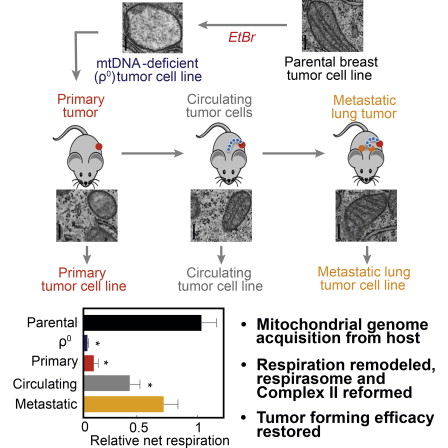

Figure 1

Tumor Cells without mtDNA Show Delayed Tumor Growth

(A) B16 and B16ρ0 cells (105) were injected s.c. into C57BL/6 or NOD/scid mice, and tumor growth was monitored. These cells and cell lines derived from s.c. tumors and lung metastases that grew from B16ρ0 cells were also injected i.v. into NOD/scid mice, and lung weight and tumor colonies were determined.

(B) 4T1 and 4T1ρ0 cells were injected s.c. or orthotopically into the mammary fat pad of Balb/c mice, and tumor growth was monitored. These cells and 6TG-resistant cell lines derived from s.c. tumors and lung metastases that grew from 4T1ρ0 cells were also injected i.v. into Balb/c mice, and lung weight and tumor colonies were determined. Images of lungs from these mice are also shown.

(C) 4T1, 4T1ρ0, 4T1ρ0SC, 4T1ρ0CTC, and 4T1ρ0SCL cells were injected into Balb/c mice, and tumor growth was monitored.

(D) Oxygen consumption by tissue of tumors derived from cells as stated above (C) was compared with respiration of liver tissue obtained from the same mice.

(E) Histological staining of tissue sections from (C) stained with H&E; scale bar, 20 μm. Data are from three independent experiments, and the results are expressed as mean ± SD. The symbol ∗ denotes significant differences with p < 0.05 and ∗∗ p < 0.001.

Highlights

- •Tumor cells lacking mtDNA form tumors only after acquiring host mtDNA

- •Tumor microenvironment instructs stepwise recovery of respiration

- •Recovery of mitochondrial function aligns with efficient tumor formation

- •Functional respirasome and complex II assembly occur in metastatic cells

Summary

We report that tumor cells without mitochondrial DNA (mtDNA) show delayed tumor growth, and that tumor formation is associated with acquisition of mtDNA from host cells. This leads to partial recovery of mitochondrial function in cells derived from primary tumors grown from cells without mtDNA and a shorter lag in tumor growth. Cell lines from circulating tumor cells showed further recovery of mitochondrial respiration and an intermediate lag to tumor growth, while cells from lung metastases exhibited full restoration of respiratory function and no lag in tumor growth. Stepwise assembly of mitochondrial respiratory (super)complexes was correlated with acquisition of respiratory function. Our findings indicate horizontal transfer of mtDNA from host cells in the tumor microenvironment to tumor cells with compromised respiratory function to re-establish respiration and tumor-initiating efficacy. These results suggest pathophysiological processes for overcoming mtDNA damage and support the notion of high plasticity of malignant cells.